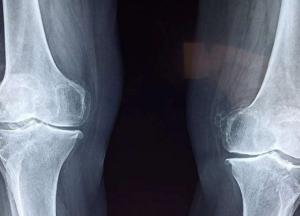

Выяснилось, что депрессивные и тревожные расстройства провоцируют снижение объема минеральных веществ, которые необходимы костям. В итоге стрессовые факторы могут в значительной степени увеличивать вероятность переломов.

Выводы, неутешительные для склонных к психоневрологическим проблемам людей, были получены по итогам экспериментального исследования, в рамках которого были созданы условия, имитирующие жизнь на космической станции. Добровольцы жили в тесном пространстве и должны были решать довольно сложные задачи, а также преодолевать конфликты с другими участниками. Все это провоцировало хронический стресс, который, как и предполагали авторы эксперимента, негативно воздействует в том числе на кости.

"При стрессе костная ткань формируется медленнее — это прослеживается по молекулам-маркерам, которые производятся в организме в процессе роста костей. Плюс, мы зафиксировали повышенный уровень норадреналина среди участников опыта", — отмечают авторы исследования.